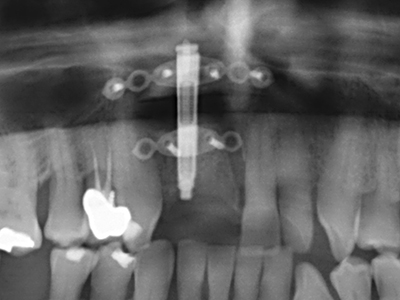

Indicazione: prelievo osseo autologo

I trapianti autologhi dell'osso si eseguono in forma di blocchi, strati e anelli, anche in combinazione con materiali di riempimento tipo microframmenti. Se il sito dell'impianto viene preparato contemporaneamente all'accrescimento, diversi sistemi di filtraggio dell'osso si sono rivelati efficaci per la raccolta dei microframmenti ossei risultanti. Come metodo alternativo, il sito dell'impianto può essere preparato utilizzando un dispositivo a bassa velocità senza irrigazione. Senza l'inserimento di un impianto, è possibile raccogliere i microframmenti ossei dalla periferia mediante bisturi affilati per tessuto osseo. Ciò può essere eseguito anche con la piezochirurgia mediante appositi raccordi che raccolgono microframmenti ossei di qualità più elevata rispetto a quelli raccolti con trapani rotondi, come è stato confermato in uno studio comparativo dei due metodi (Chiriac, Herten et al. 2005).

La piezochirurgia presenta altri vantaggi per quanto riguarda la raccolta di blocchi ossei. Oltre all'elevata precisione dell'osteotomia appena descritta, l'utilizzo di puntine per sega molto sottili permette di minimizzare in maniera significativa la perdita di materiale. È molto probabile che si verifichi una maggiore perdita di materiale durante la raccolta utilizzando puntine di strumenti più spessi, in particolare delle frese Lindemann (Lakshmiganthan, Gokulanathan et al. 2012). La separazione basale, necessaria in particolare per i trapianti di blocchi nella zona retromolare, viene semplificata grazie a seghe specificatamente progettate di forma rettangolare; di conseguenza la piezochirurgia è considerata una procedura precisa, semplice e sicura per la raccolta di blocchi di osso nella zona retromolare (Happe 2007) (figg. 1-12).